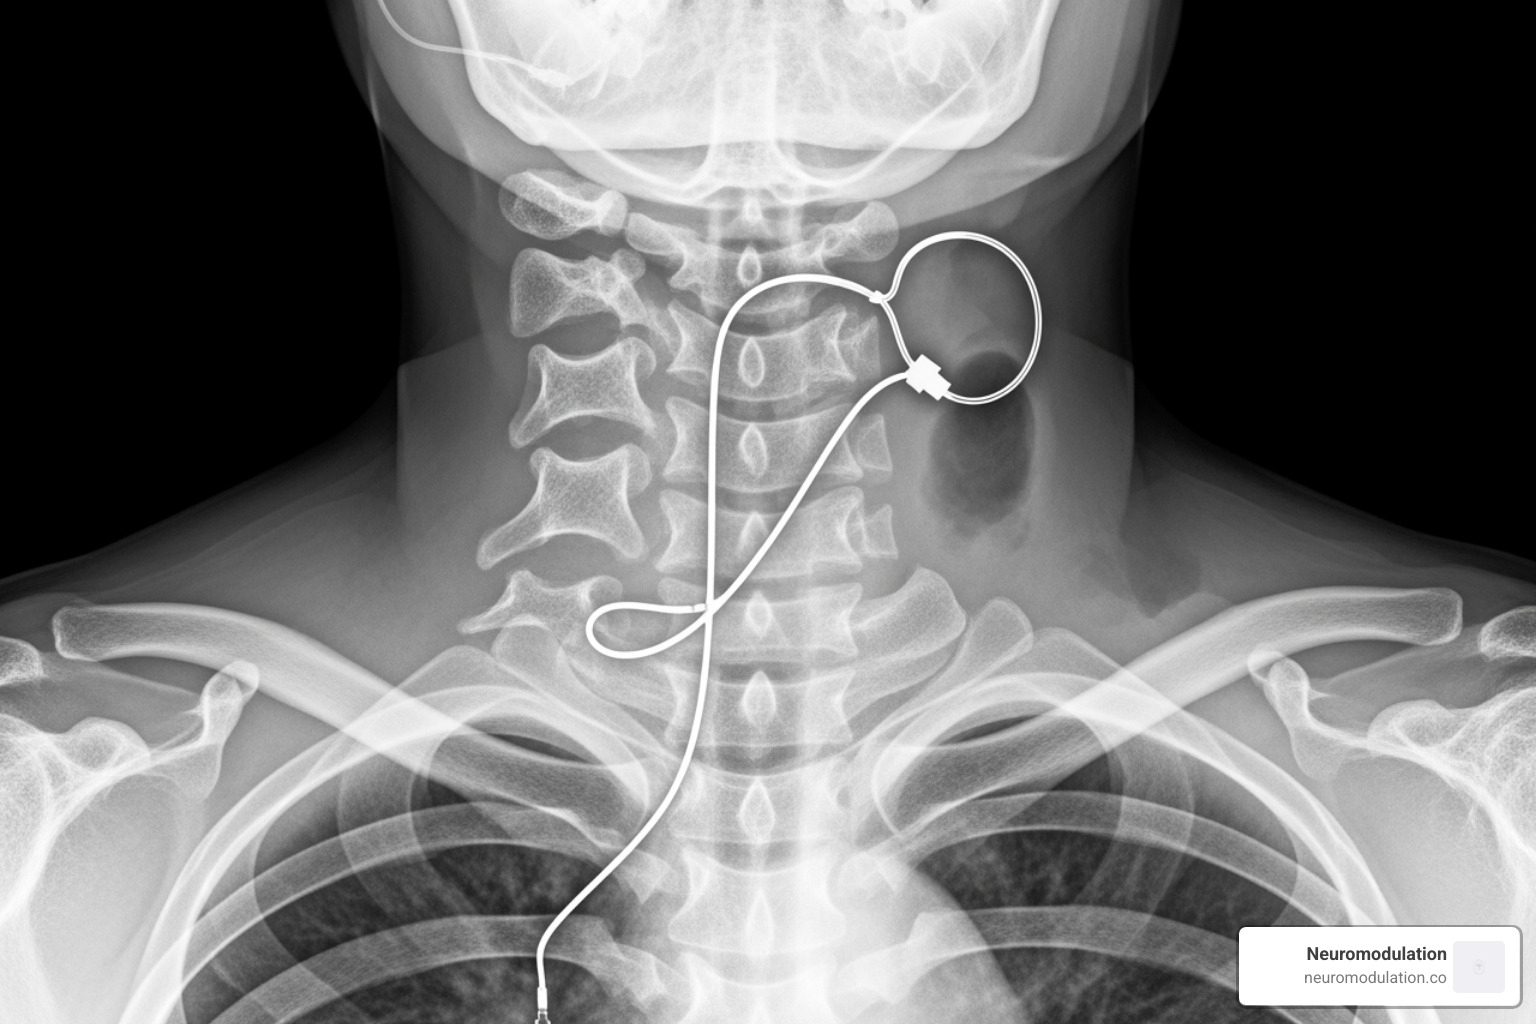

While your chest X-ray shows two-thirds of the story, we need a separate neck X-ray to see the third critical piece: the stimulation lead that actually treats your sleep apnea.

Your neck radiograph reveals this fine wire extending upward from your chest device, traveling under your skin like a hidden highway, until it reaches its destination in the area under your chin called the submandibular region.

The magic happens at the end of this lead – a tiny cuff electrode that your surgeon carefully wrapped around a branch of your hypoglossal nerve. This is the twelfth cranial nerve, and it controls all the muscles that move your tongue.

On your lateral neck X-ray, we can trace this lead’s path and make sure it follows a smooth, natural curve without any sharp bends or kinks. The cuff itself might appear as a small bright spot encircling the nerve, though sometimes it’s quite subtle.